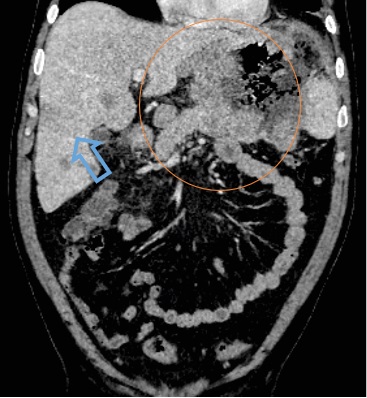

Для определения объема поражения пациенту проведено комплексное компьютерно-томографическое исследование органов грудной клетки, брюшной полости и забрюшинного пространства, полости малого таза (рис. 1).

Рис. 1. Компьютерная томография органов брюшной полости: коронарная проекция, где определялось бугристое, диффузное, циркулярное неравномерное утолщение стенок желудка (оранжевый круг). Множественное очаговое поражение печени (синяя стрелка)

Примечание: изображение авторов.

При первичном исследовании на КТ-сканах органов брюшной полости было выявлено образование стенок желудка, вторичное поражение печени, лимфаденопатия парагастральных лимфоузлов. По данным КТ головы, шеи органов грудной полости и полости малого таза данных за вторичное поражение, лимфаденопатию не выявлено.